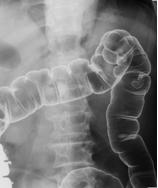

| 大腸の消化管X線造影検査です。大腸の中の便をきれいに排出しておかなければならないので、検査の前々日から検査食や下剤を飲んで検査の準備をする必要があります。検査前に大腸のはたらきを抑える注射をし、造影剤のバリウム液と空気を肛門から注入し、腸の粘膜にバリウムを付着させます。この検査ではがんやポリープなどが見つかります。食生活が欧米化し大腸がんが増えています。検診では、便潜血反応検査を行い、検査が陽性のとき、下部消化管X線造影検査や、内視鏡検査を行います。 | ![]() |

| 大腸の二重造影像 |